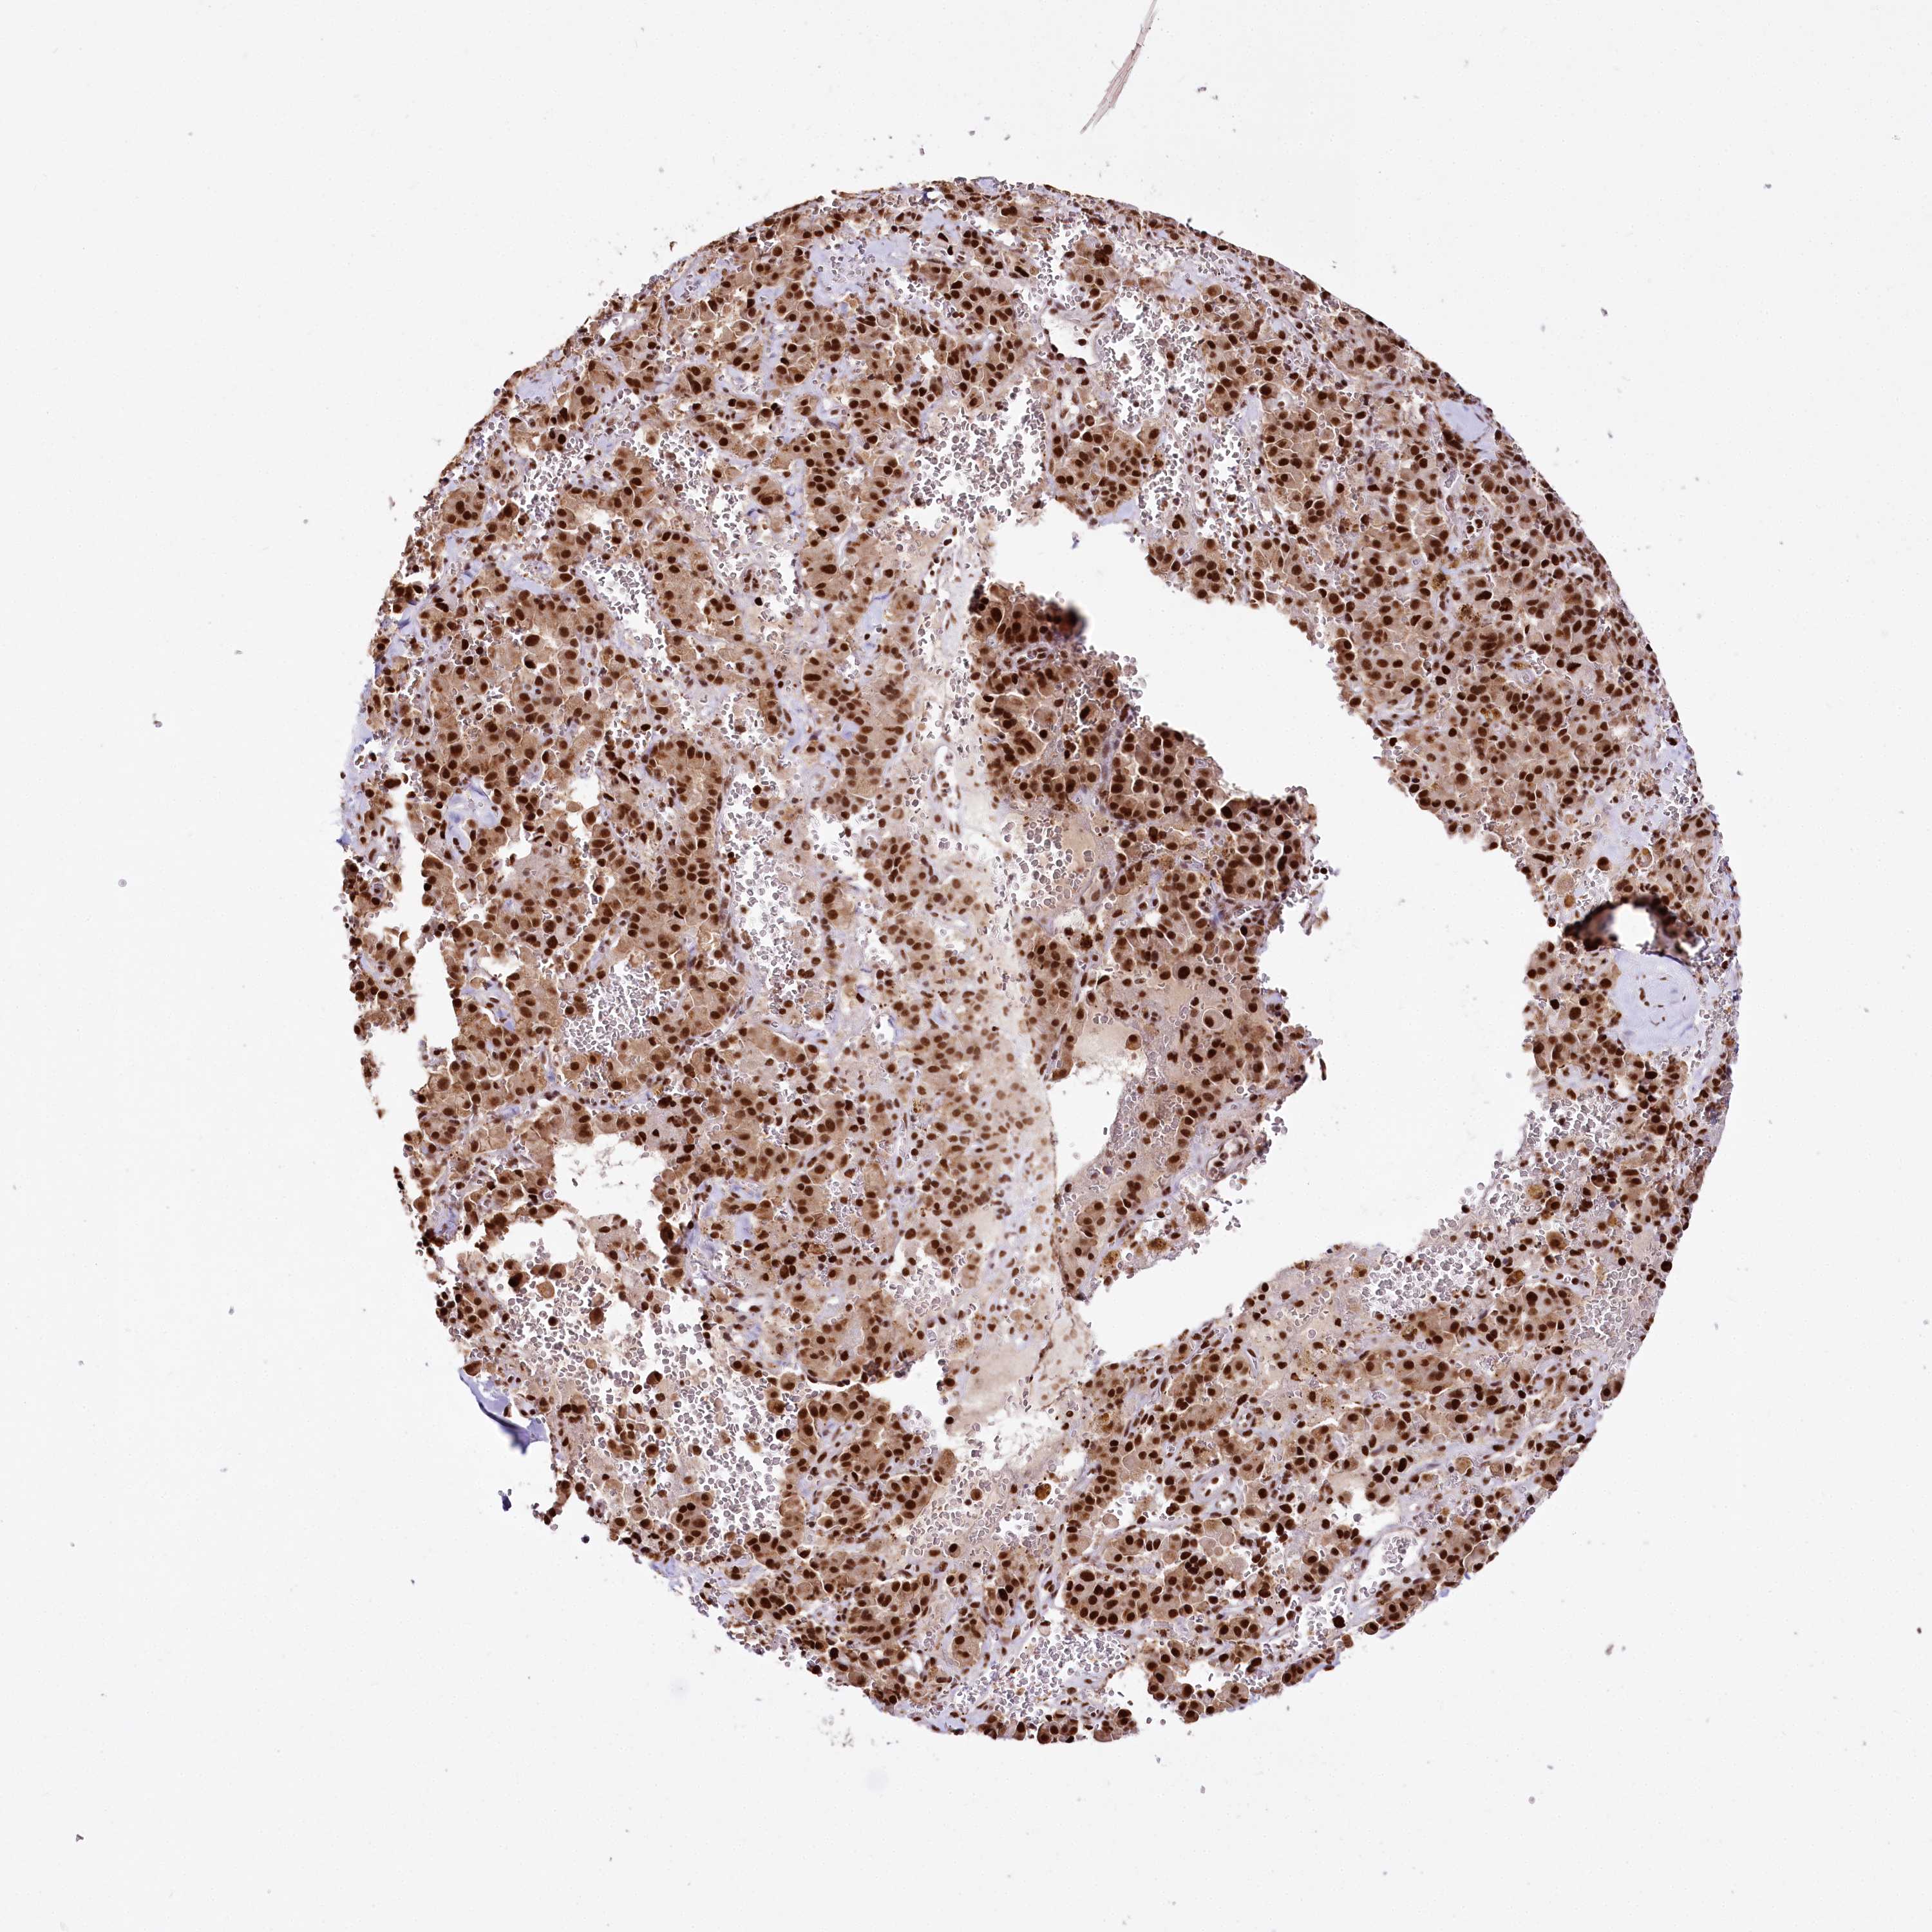

PANCREATIC CANCER - Protein expressioni

A mouse-over function shows sample information and annotation data. Click on an image to view it in a full screen mode. Samples can be filtered based on level of antibody staining by selecting one or several of the following categories: high, medium, low and not detected. The assay and annotation is described here.

Note that samples used for immunohistochemistry by the Human Protein Atlas do not correspond to samples in the TCGA dataset.

Antibody stainingi

Antibody staining in the annotated cell types in the current human tissue is reported as not detected, low, medium, or high, based on conventional immunohistochemistry profiling in selected tissues. This score is based on the combination of the staining intensity and fraction of stained cells.

Each image is clickable and will lead to virtual microscopy that enables deeper exploration of all samples and also displays staining intensity scores, fraction scores and subcellular localization as well as patient and tissue information for each sample.

Antibody HPA003916

Antibody CAB037318

Staining

High

Medium

Low

Not detected

Intensity

Strong

Moderate

Weak

Negative

Quantity

>75%

75%-25%

<25%

None

Location

Nuclear

Cytoplasmic/membranous

Cytoplasmic/membranous,nuclear

Adenocarcinoma, NOS

Adenocarcinoma, metastatic, NOS